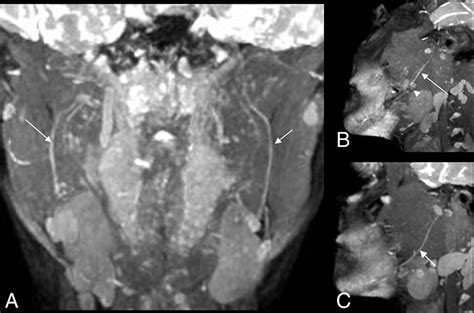

To overcome this, this specialized imaging employs specific pulse sequences designed to suppress the signal from fat—which often obscures nerve detail—while enhancing the signal from water-rich tissues like nerves. This process effectively makes the nerves "light up" on the resulting images, allowing radiologists to assess their anatomy, signal intensity, and trajectory in high detail.

Once the images are acquired, they are analyzed by a radiologist with specialized expertise in musculoskeletal or neuroradiology. The goal is to identify changes in the nerve's appearance. For instance, a healthy nerve typically appears as a thin, uniform structure with a consistent signal. In contrast, an injured or compressed nerve may exhibit:

• Increased signal intensity: Often indicative of edema (swelling) or inflammation within the nerve.

• Nerve enlargement (fascicular thickening): A sign that the nerve is being subjected to chronic pressure or trauma.

• Discontinuity or disruption: Clearly visible in cases of severe trauma or nerve rupture.

• Masses or Lesions: Clear identification of tumor growth within or adjacent to the nerve sheath.